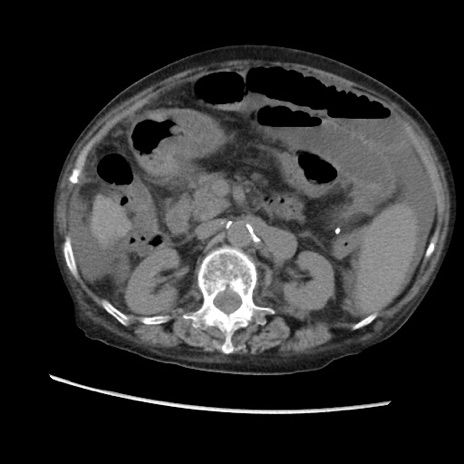

冠状断像

【症例】80歳代 女性

【主訴】腹部膨満感

【現病歴】他院にて肝硬変にてフォロー中。1週間前から便秘、腹部膨満感、臍部腫瘤あり受診となる。

【既往歴】肝硬変

【身体所見】腹部膨隆あり、皮膚変化なし、疼痛なし。

【データ】WBC 4600、CRP 0.25